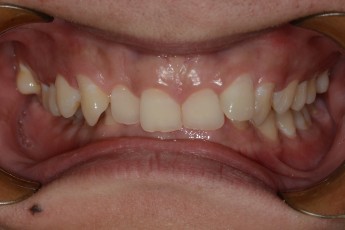

Before

After